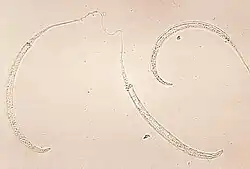

| Photomicrograph of larvae | |